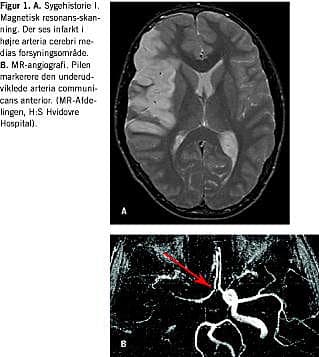

På grund af progredierende symptomer foretog man magnetisk resonans (MR)-skanning af cerebrum, og ved skanningen kunne man påvise iskæmiforandringer i højre hemisfære svarende til a. cerebri medias forsyningsområde. Ved angiografi sås der intet flow i højre a. carotis interna og kun sparsomt flow i højre a. cerebri media og enkelte af dennes forgreninger. Circulus Willisii (circulus arteriosus cerebri) fandtes inkomplet med en underudviklet a. communicans anterior (Figur 1 ).

II: En 19-årig mand fik to måneder efter svært hovedtraume i forbindelse med bilulykke foretaget en MR-skanning. Patienten var på dette tidspunkt indlagt til rehabilitering på Afsnit for Traumatisk Hjerneskade, i langsom opvågning og med højresidig hemiparalyse. MR-skanningen viste diffus aksonal skade, en blødning i venstre basalganglieområde, og overraskende - dissektion og total okklusion af højre a. carotis interna i dennes intrakranielle forløb. Der fandtes ingen intrakranial carotisfyldning, men pæn fyldning af a. cerebri media og ingen iskæmiske forandringer i parenkymet. Circulus Willisii fandtes komplet med en veludbygget a. communicans anterior.